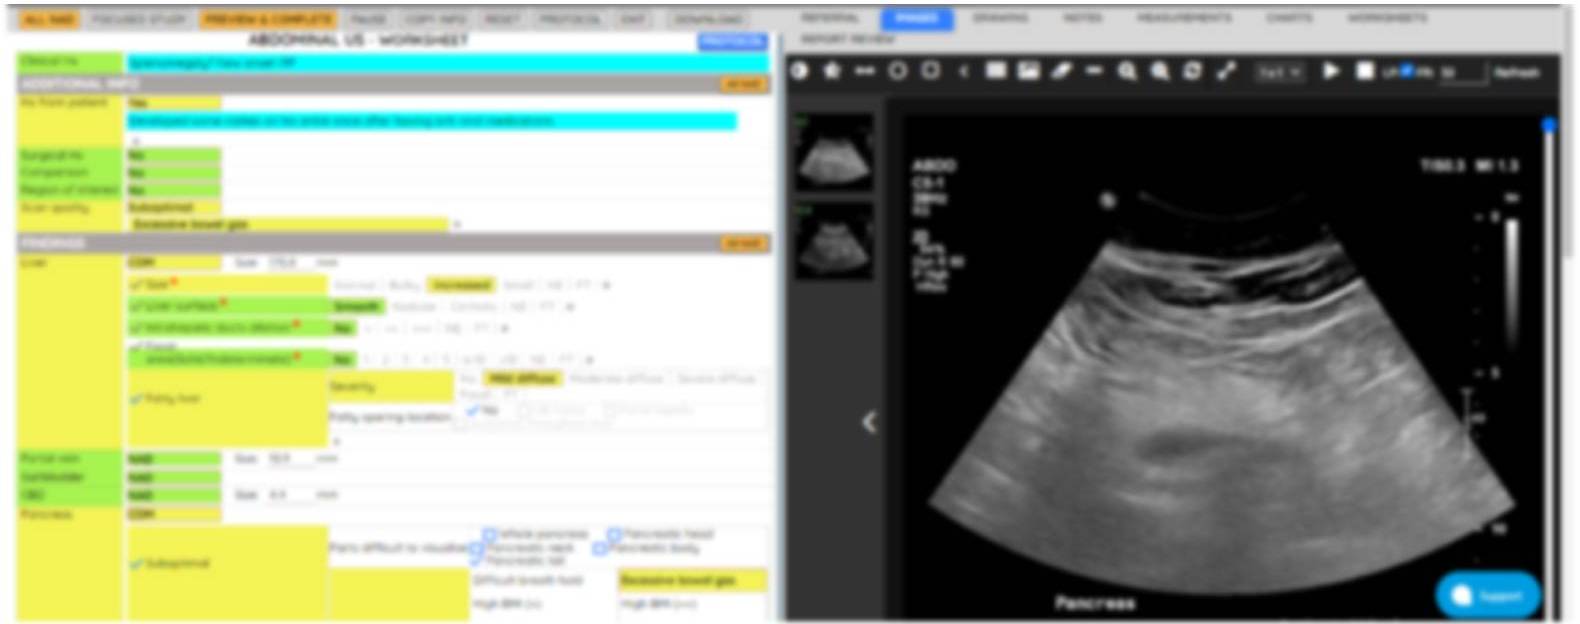

Our General & Small Parts Ultrasound service offers comprehensive and detailed imaging solutions to aid in accurate diagnosis and treatment planning. Each worksheet is designed with precision and embedded with advanced calculation packages and charts to provide the best possible insights.

Embedded calculation packages, charts, and high-resolution imaging enhance diagnostic accuracy.